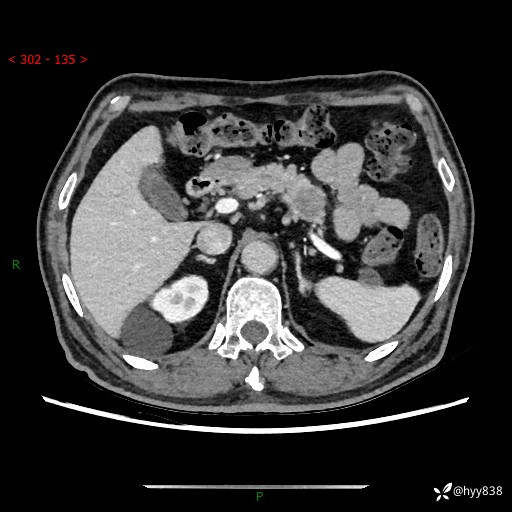

69岁/男,四肢无力3月余。胰腺囊实性占位,渐进性强化---结果公布~

【患者信息】:69岁/男

【主诉】:四肢无力3月余。

【现病史及既往史】:患者3月前无明显诱因出现四肢乏力,伴有口干、多饮、多尿等症状,无畏寒、发热、恶心、腹痛、腹泻等其他症状,于2024-06-13来我院住院治疗,完善相关辅助检查后,考虑“2型糖尿病”,予以降糖(阿卡波糖片 50mg po tid、德谷门冬双胰岛素注射液 8iu 早餐前 皮下注射)等治疗,口干、多饮、多尿较前缓解,血糖控制可;现仍存在四肢乏力,于2024-08-28来我院门诊就诊,查血钾2.88 mmol/L ,现以“低钾血症”收入我科。 本次起病以来,患者精神、饮食、睡眠良好,二便正常,近3月余体重下降约5kg。

【检查】:胰腺CT平扫+增强